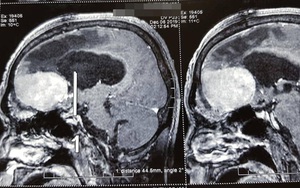

Sống khỏe 2019-12-12T19:37:00Người đàn ông 62 tuổi trước đó đã đi điều trị tâm thần nhiều năm. Sau khi được phẫu thuật khối u não bệnh nhân đã không còn điên dại.